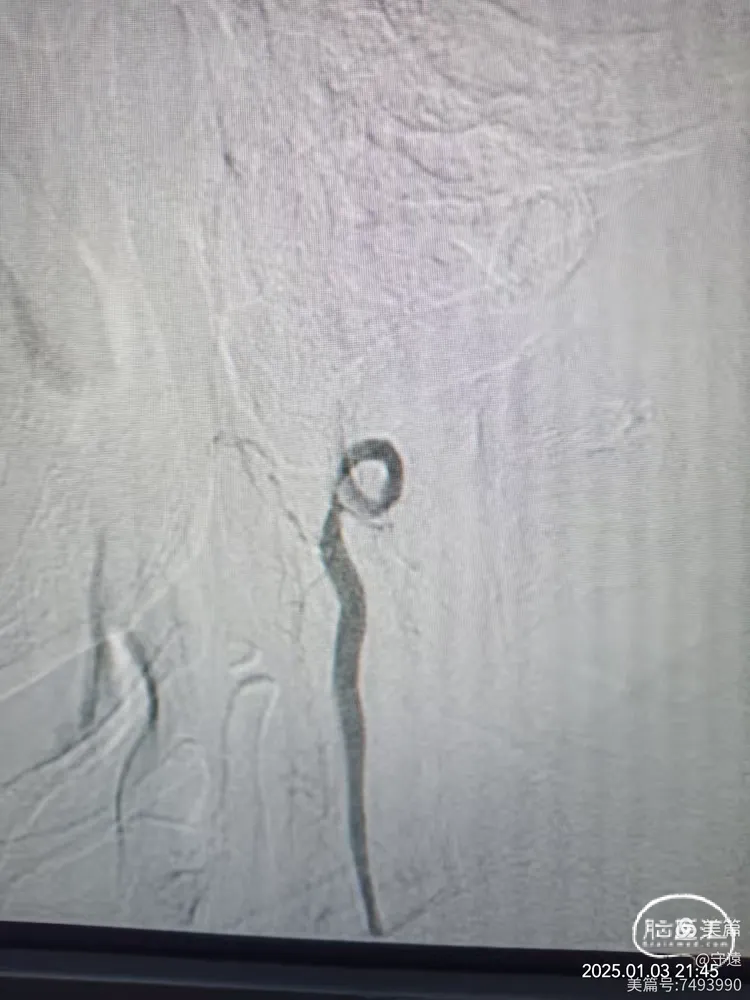

右侧椎动脉顺应,更换6F动脉鞘经桡动脉入路行基底动脉开通。

泥鳅导丝导引6FGT68血栓抽吸导管,泥鳅导丝不出头,内芯支持抽吸导管到达V3段。

踹马桶抽吸出小块硬质血栓。

微导管造影显示Ⅴ4狭窄。

微导丝携带2.5*15mm球囊在V4~基底动脉下段扩张。

撤出球囊血管,造影显示再次闭塞,考虑夹层或回弹可能。

球囊穿梭:跟进抽吸导管至狭窄部位,再次输送球囊至狭窄部位。球囊半含状态下再次在7个大气压下扩张。

撤出球囊,踹马桶抽吸出暗红色血栓。

微造影显示:血管再通

回撤导管至V3段造影,狭窄不明显,血流通畅。